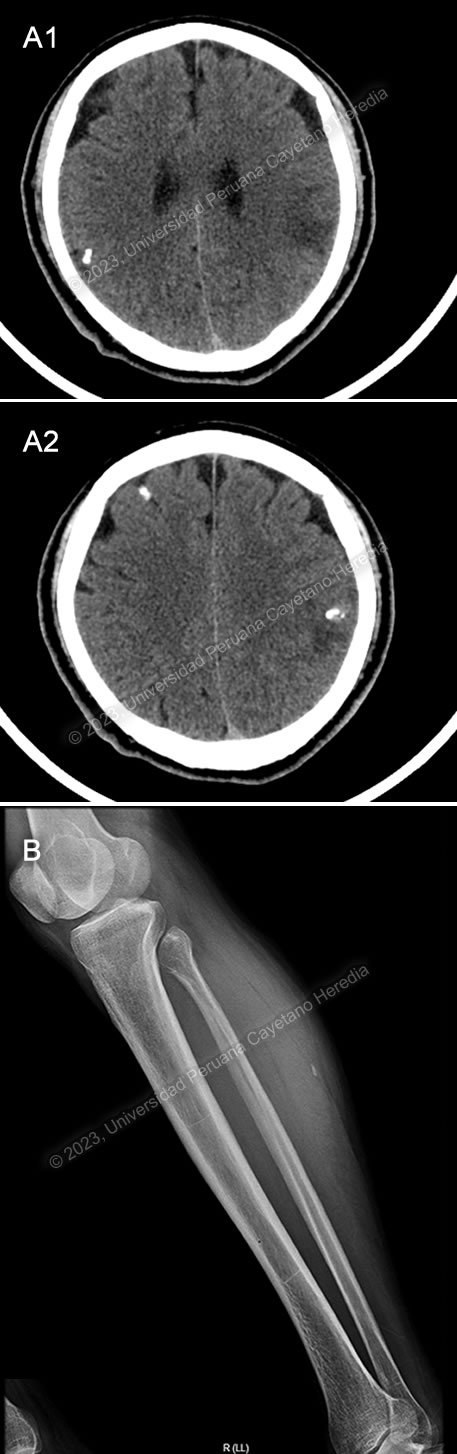

Diagnosis: Parenchymal neurocysticercosis

![]() Discussion: Brain CT showed a calcified lesion with surrounding edema in the left parietal lobe and additional calcified nodular lesions with no edema in the left occipital lobe. The lower limb x-ray showed a cigar-shaped calcification compatible with a calcified cysticercus. Brain MRI (Image C) confirmed these findings, showing an irregular nodular cortico-subcortical lesion of heterogenous aspect with peripheral vasogenic edema in the left parietal lobe, and the previously described left occipital lesions. A diagnosis of neurocysticercosis was made with these images. |